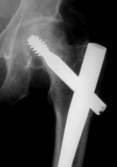

Das Ergebnis ist eine Fehlplazierung der Schenkel- halsschraube Diese korrekte Lage wurde mit dem neuartigen Zielgerät erreicht. Das neue Zielgerät läßt sich leicht auf dem Obturator befestigen und zielt sowohl in der Aufsicht, als auch in der Seitaufnahme. Links ist die falsche Position und rechts durch Drehung des Zielgerätes die korrekte Position zu sehen. Liegen die drei Drähte nun zu weit Proximal, muß der Nagel wieter nach distal geschoben werden.

Position des Gerätes in seitlicher Lage ergibt beim Röntgen die folgenden Aufnahmen. Der geriffelte Draht liegt nicht zwischen den zwei glatten Drähten. Bewegen des Zielgerätes ergibt das erforderliche Bild. Sollten die so positionierten Drähte sich nicht über dem Kopf abbilden, muß der Nagel gedreht werden. Auf diese Weise erreicht man die korrekte Lage der Schenkelhalsschraube in die Mitte des Kopfes, ein Auswandern der Schraube ist so unmöglich.